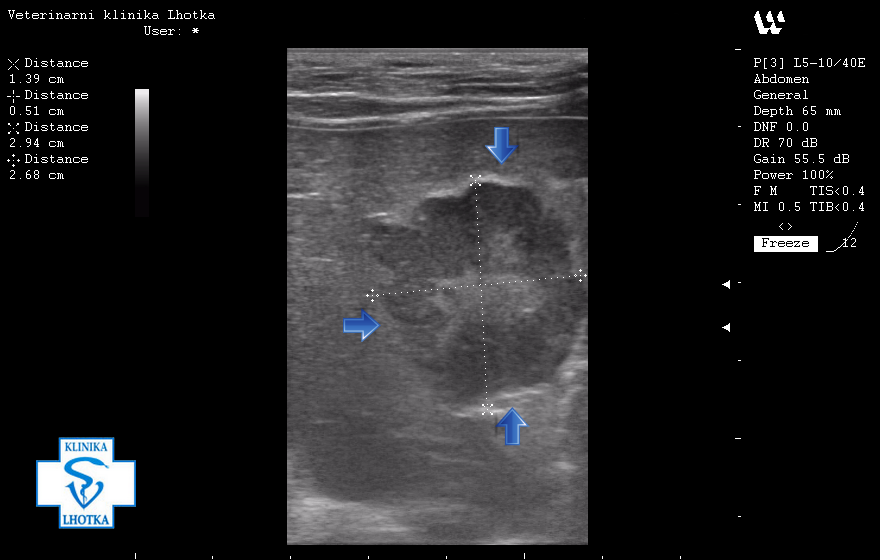

Na ultrazvukových snímcích jsou šipkami označeny metastázy v oblasti jater, levé ledviny, pravděpodobně i v močovém měchýři a v mízních uzlinách pod bederní páteří.

Na pravé straně je šipkou a šrafováním vyznačen obrys levé ledviny. Na levé straně modrá šipka ukazuje na kulovitý útvar, pravděpodobně metastázu v kůře ledviny.

SONO - metastáza v ledvině